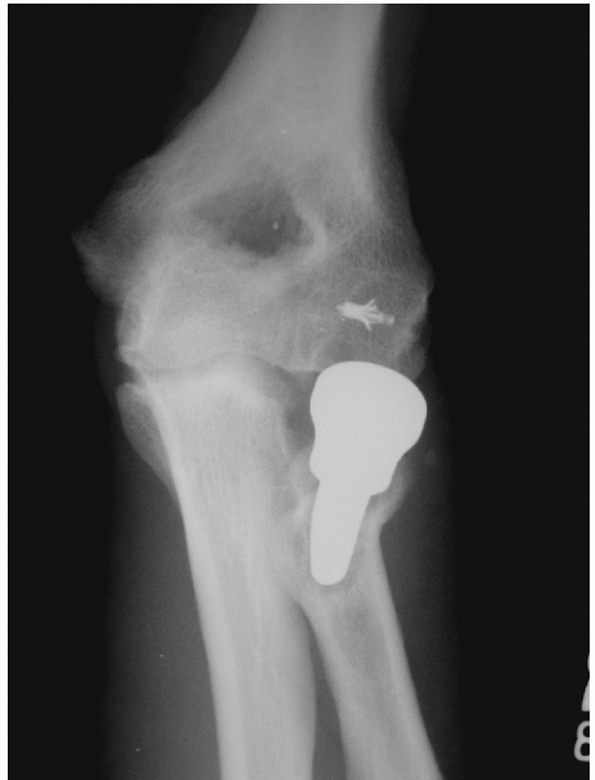

FIGURE 32-18 Small coronoid fractures are often problematic. A. This appears to be a small isolated fracture of the coronoid. B.

On the anteroposterior view, it is clear that the anteromedial facet of the coronoid process is fractured. There is varus subluxation and opening of the joint on the lateral side betraying the associated lateral collateral ligament injury. C. Three-dimensional computed tomography depicts external rotation of the distal humerus with respect to the forearm as the trochlea rotates forward into the coronoid defect. D. There are separate coronoid tip and anteromedial facet fracture fragments. (continues) |

FIGURE 32-18 (Continued) E.

Exposure is obtained by transposing the ulnar nerve anteriorly and elevating the anterior portion of the flexor-pronator muscles off of the medial collateral ligament and the coronoid process. F. The coronoid fractures were secured with a buttress plate and the lateral collateral ligament origin was reattached to the lateral epicondyle with a suture anchor. G. A concentric reduction and good elbow function resulted. |